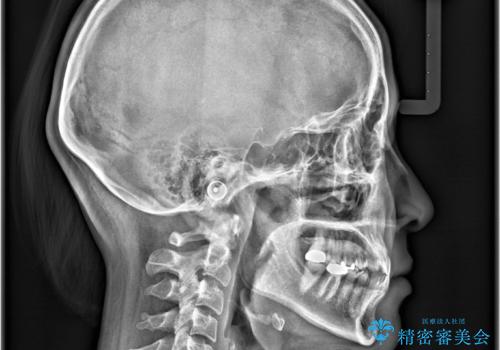

- すきっ歯と切端咬合(上下の前歯が先端で当たるかみ合わせ)を主訴にご来院された患者様です。

矯正検査を行った結果、非抜歯でインビザラインによる治療が可能と判断し、マウスピース矯正で改善を行いました。

11ヵ月で矯正治療が終了し、前歯の隙間も改善、見た目とかみ合わせも良好な状態となり、患者様にも大変ご満足いただけました。